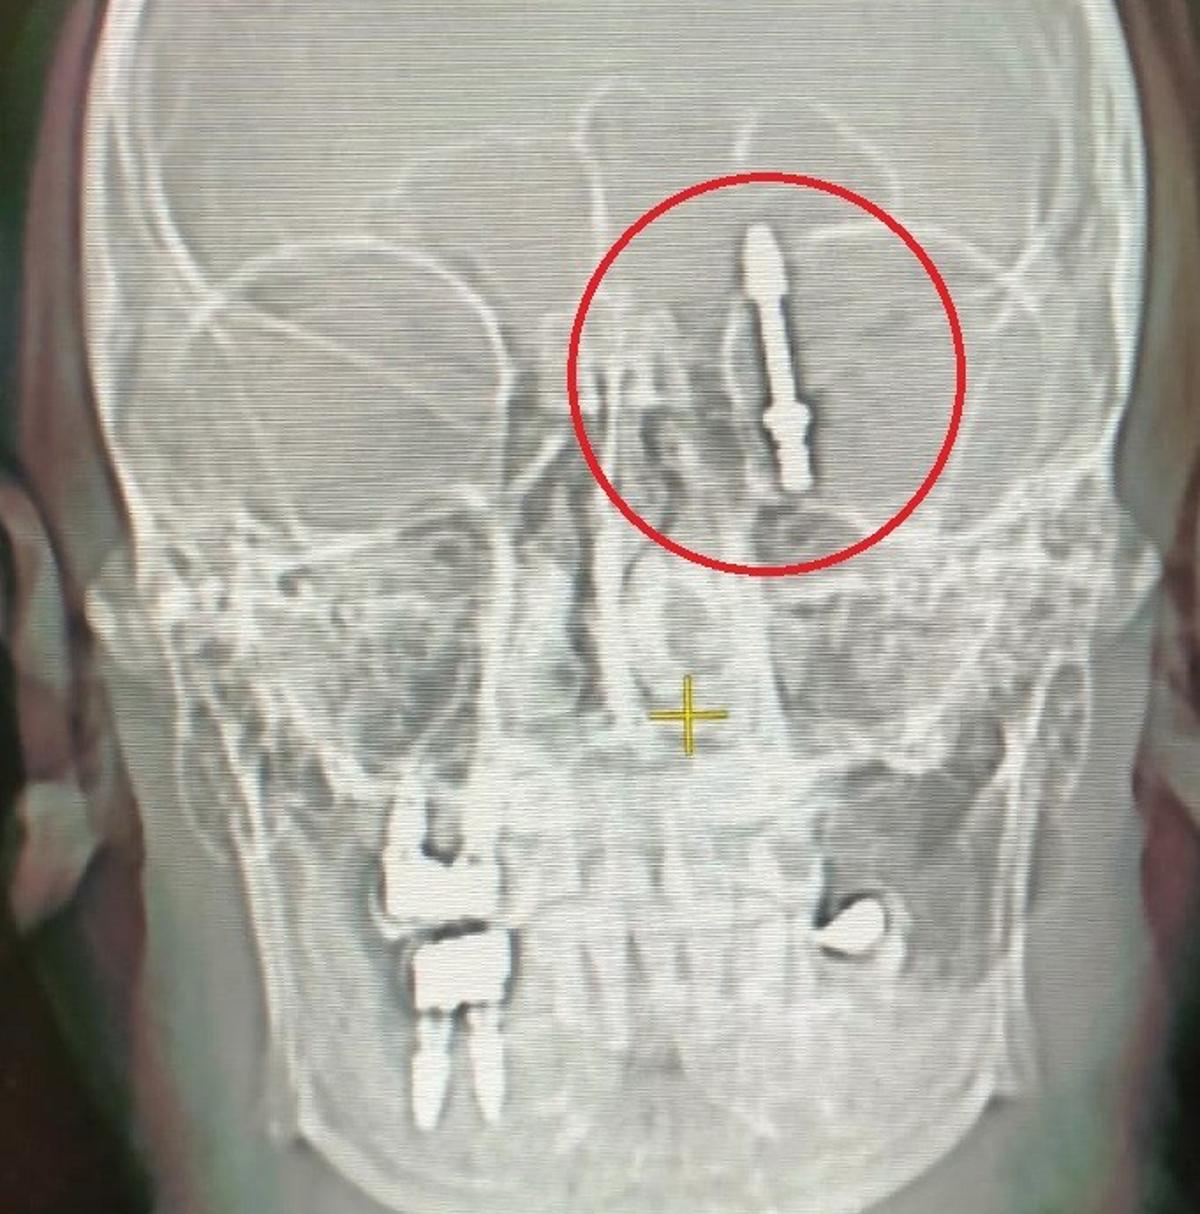

Nilüfer ilçesinde özel bir diş kliniğinde muayene olan Yılmaz'a, dişlerinin sallandığı gerekçesiyle implant tedavisi önerildi. Ancak iddiaya göre, doktor A.D.'nin hatalı müdahalesi sonucu implant vidası çene kemiğini delip kafatasına saplandı.

Baygınlık geçiren Yılmaz, kliniğin kendi aracıyla hastaneye kaldırıldı. Tomografi çekiminde vidanın beynine kadar ilerlediği ortaya çıktı. Acil ameliyata alınan talihsiz adam, saatler süren operasyonla ölümden döndü.